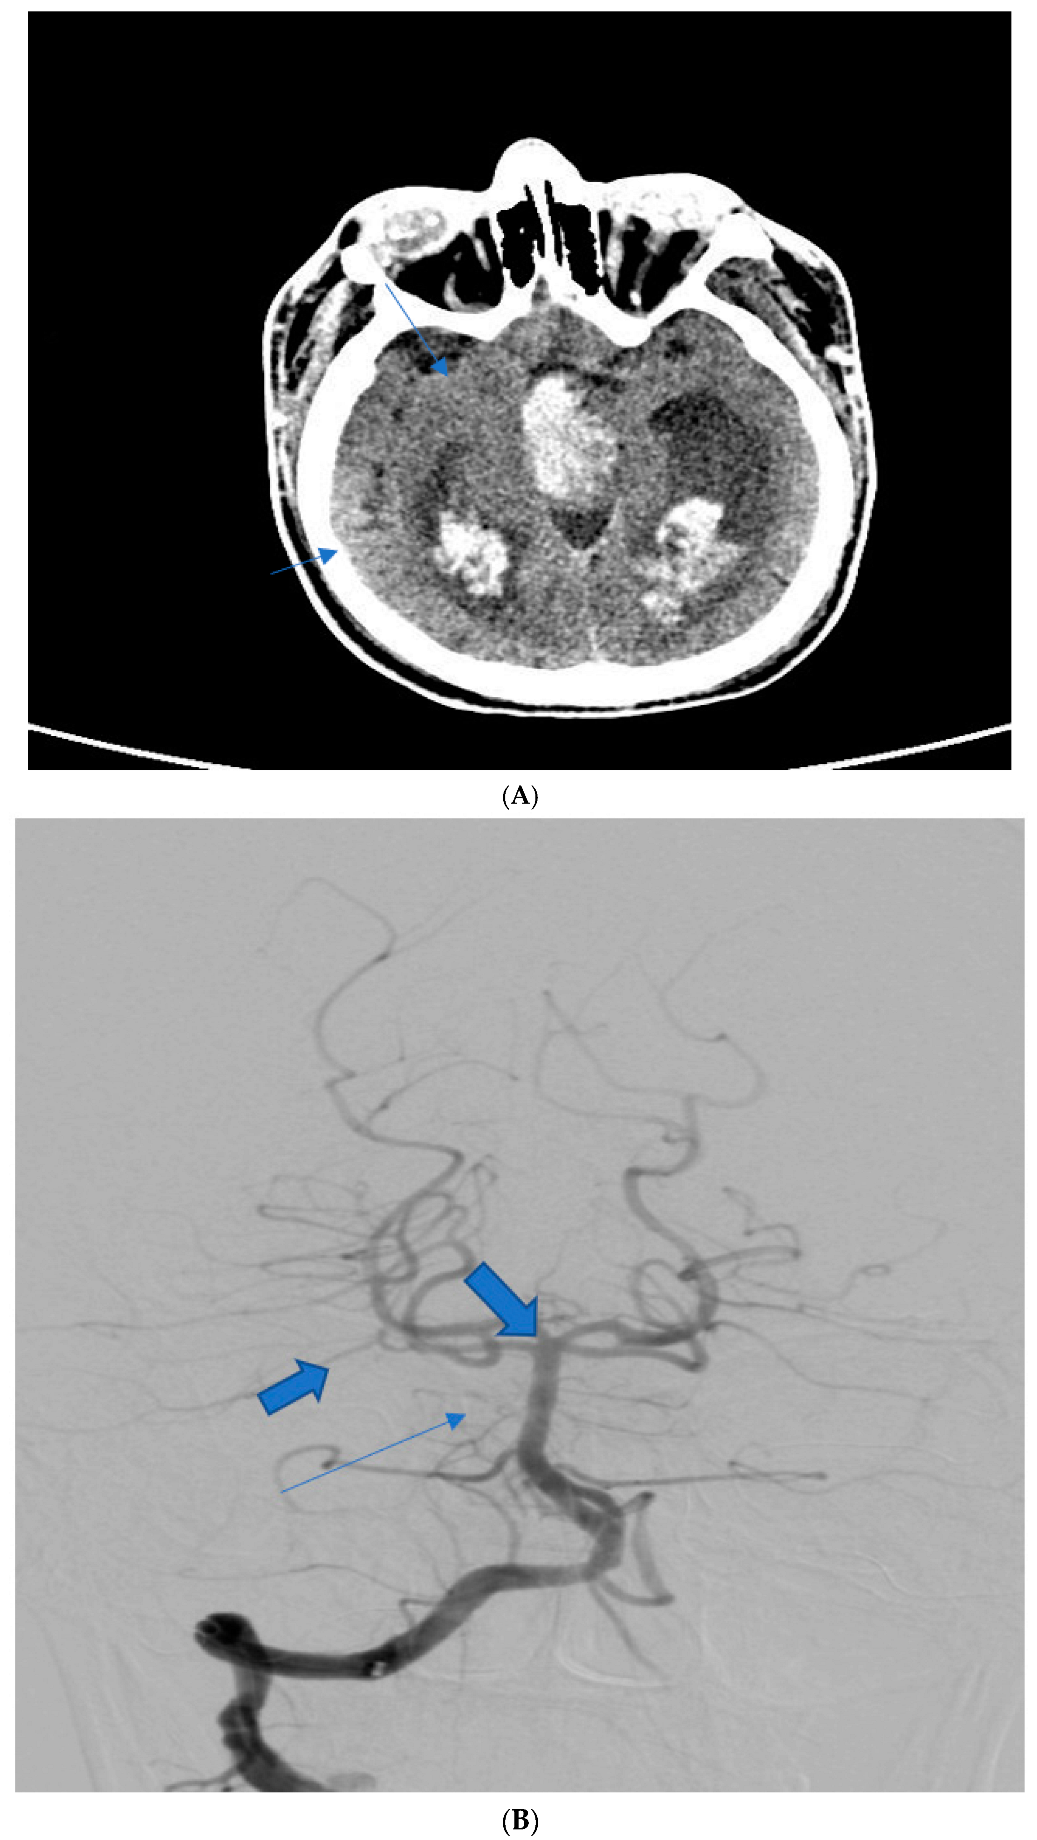

| Patient Age | Patient Sex | Presenting Symptoms | Diagnosis Method | Hunt Hess Scale at Diagnosis | Modified Fischer Scale at Diagnosis | Complications | Rankin Scale at Discharge | Given Treatment |

|---|---|---|---|---|---|---|---|---|

| 54 | F | Diplopia, headache | Native CT scan, CTA | I | I | Mild vasospasm, mild hydrocephaly | 2 | Nimodipine |

| 61 1 | M | Flaccid tetraplegia, altered Mental status | Native CT scan, DSA | IV | IV | Severe vasospasm, hydrocephalus | 6 (deceased) | Nimodipine, mannitol |

| 37 | M | Headache, diplopia | Native CT scan, DSA angiography | II | II | None | 3 | Nimodipine |

| 48 | F | 3rd nerve palsy, pupillary anomalies | Native CT scan, CTA | II | II | Mild vasospasm | 2 | Nimodipine |

| 41 2 | M | Headache, diplopia | Native CT scan, DSA | III | III | Mild vasospasm | 3 | Nimodipine, mannitol |

| 59 | M | 3rd nerve paresis, pupillary anomalies, hemiplegia | Native CT scan, DSA angiography | V | IV | Hydrocephalus, moderate vasospasm | 4 | Nimodipine, mannitol |

| 44 | F | Right internuclear ophthalmoplegia | Native CT scan, CTA | III | I | None | 1 | Nimodipine |